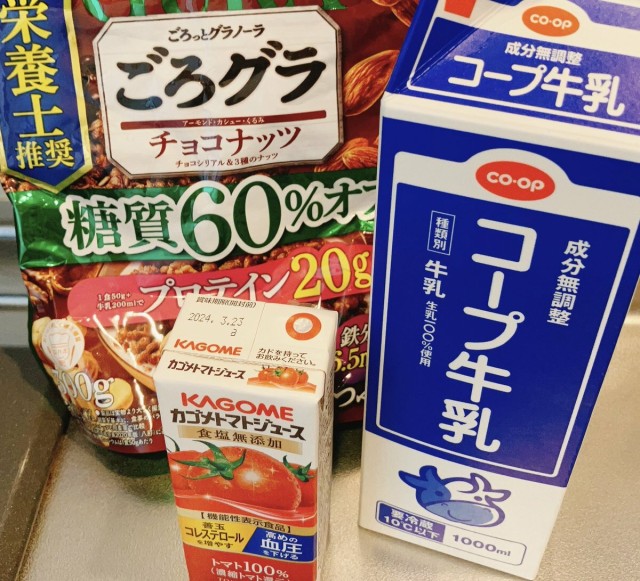

妊娠中の食事 妊娠糖尿病 再検査まで8日 〜あさごはん〜 起床して水 トマトジュース→ごろグラ糖質オフ50g +牛乳200ml 20分かけて食事 トマトジュース飲んでから少し間あけたくて、飲み終わってからごろグラ準備してる なんか満腹感が違う気がする。